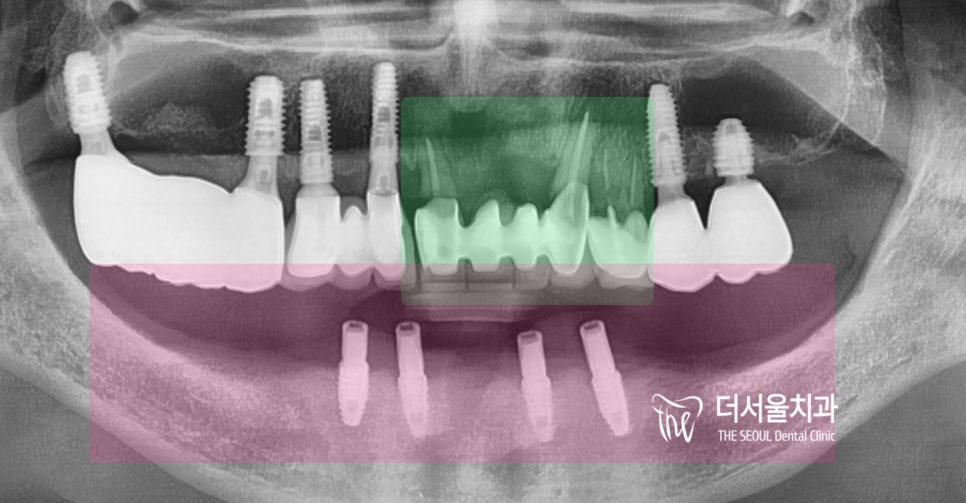

그리고, 이미 하악에는

overdenture 라는 임플란트 에

틀니를 연결해서 쓰는 보철을 끼고 계셨네요.

* 초록색 : 임플란트 수술을 해야 될 곳

* 핑크색 : 틀니를 끼고 있는 곳

예측 된 값에 따라서 예측 된 위치에

그대로 고정체들을 심어드렸으며

3개월 뒤, 골 치유에 따라서

지르코니아 보철을 올려드렸으며

예쁜 스마일 라인 완성입니다.^^